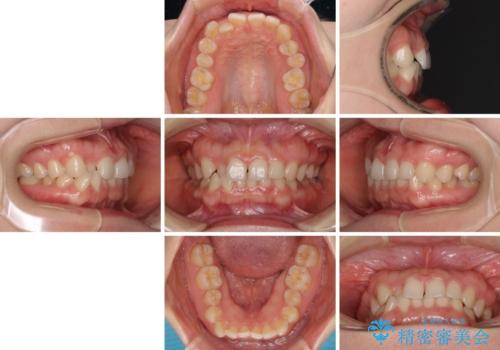

- 前歯の隙間やクロスバイトを気にして来院された患者様です。

結婚式の予定があり、可能であれば結婚式までに治療を終えたいとのことで、短期間で治療をおける可能性の高いワイヤー装置にて矯正治療を行うこととしました。